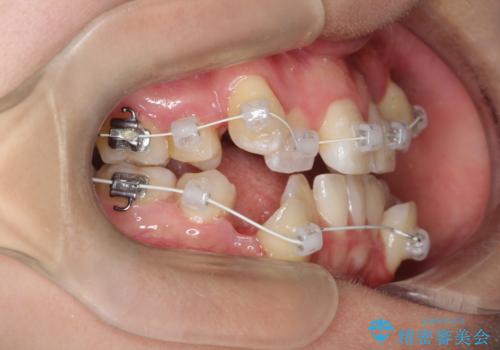

【ワイヤー矯正】八重歯 歯のでこぼこを治したい!

- 治療計画

- 「歯のでこぼこを治したい」を主訴に来院された患者様です。 上下ともに、歯のでこぼこが強く、上下左右4の抜歯をし、ワイヤー矯正で治療を行いました。

かなり綺麗に並ぶ事ができ大変満足していただけました。

叢生量がかなり多かったのですが、歯肉退縮も失活歯も無くとても綺麗な歯並びになりました。